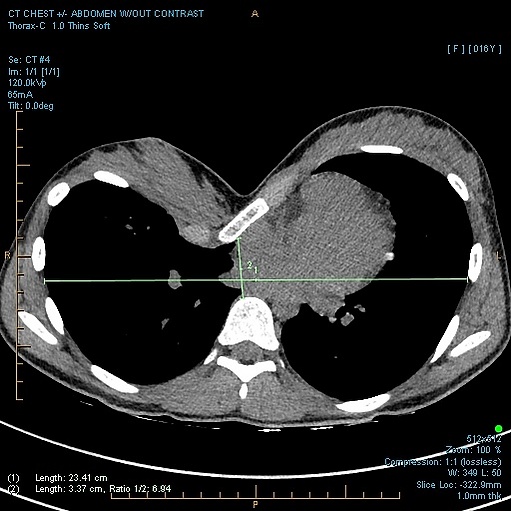

Степень тяжести ВДГК по индексу Халлера (КТ-индекс). Индекс рассчитывают путём деления максимального фронтального размера грудной клетки на наименьшее расстояние между задним контуром грудины и передним контуром позвоночника. Расчёт индекса Халлера производят по КТ, выполненной в горизонтальном срезе В норме индекс равен 2,5. При показателях более 3,25 показано оперативное лечение.[4]

- КТ и МРТ необходимы для точной оценки степени деформации грудной клетки[2][5].